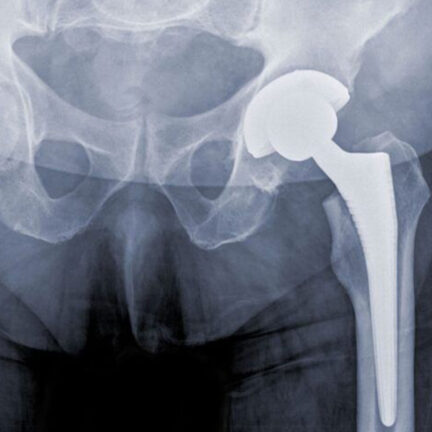

Αρθροπλαστική Ισχίου

Η αρθροπλαστική ισχίου βελτιώνει την κινητικότητα και μειώνει τον πόνο, αντικαθιστώντας την φθαρμένη άρθρωση με τεχνητή, για καλύτερη ποιότητα ζωής.

ΠΕΡΙΣΣΟΤΕΡΑ